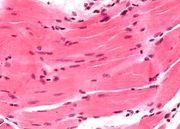

| 03:24, 20 июля 2016 | Mishci sport75.jpg (файл) |  |

53 КБ | Anes | Микроскопическое строение кардиомиоцита | 1 |